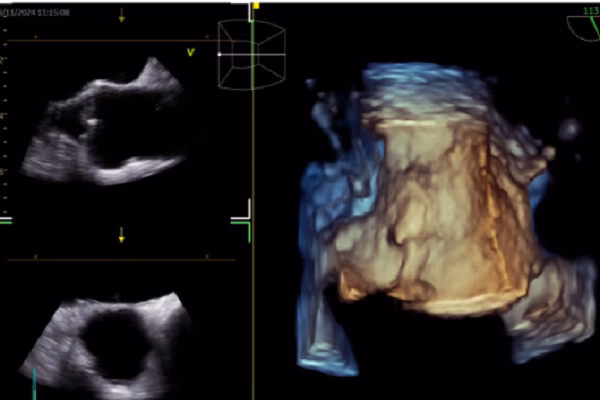

Trong ECG, AI được sử dụng để dự đoán các tình trạng như rung nhĩ, suy tim có phân suất tống máu giảm và hẹp van động mạch chủ. AI cũng giúp nhận diện các bất thường trong nhịp tim và cảnh báo các bác sĩ về các tình trạng nguy hiểm tiềm ẩn. Trong siêu âm tim, AI giúp nhận diện cấu trúc cơ tim, đo đạc tự động và hỗ trợ báo cáo và chẩn đoán. AI cũng có thể giúp các bác sĩ đánh giá chức năng tim mạch và xác định các bất thường trong cấu trúc tim.